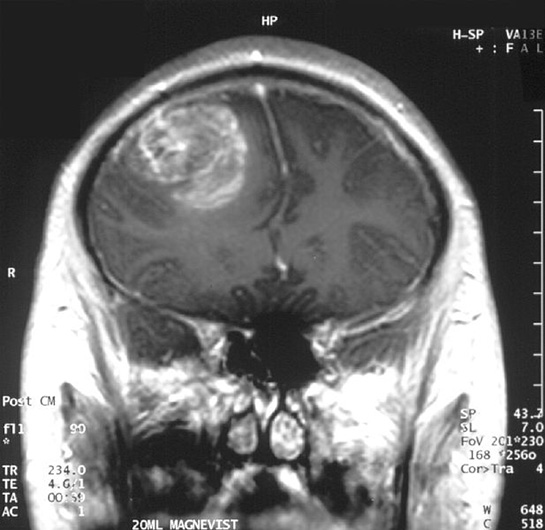

Beyin tümörleri, hücre tipine ve tümörün bulunduğu bölgeye göre farklı sınıflara ayrılır. Bu sınıflandırma, tedavi yöntemlerini ve prognozu etkileyen önemli bir faktördür. Aşağıda beyin tümörü çeşitleri hakkında detaylı bilgiler sunulmaktadır: - Primer Beyin Tümörleri: Bu tümörler, beyin dokusunda doğrudan gelişen tümörlerdir. Çeşitleri arasında

- Astrositom: Beyin hücrelerinden (astroglia) gelişir ve farklı derecelerde malignite gösterebilir.

- Glioblastom: En yaygın ve en agresif beyin tümörü türüdür. Genellikle hızlı büyür ve tedavi edilmesi zordur.

- Meningiom: Beynin zarlarında (meninks) gelişir ve genelde iyi huyludur, ancak büyüdüğünde beyin dokusuna baskı yapabilir.

- Medulloblastom: Özellikle çocuklarda görülen, serebellumda (beyin arka kısmı) gelişen malign bir tümördür.

- Schwannom: Sinir hücrelerinden kaynaklanır ve genelde iyi huyludur, ancak sinirlerde sıkışma yapabilir.